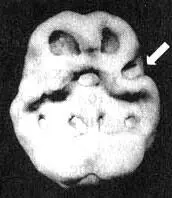

Первая попытка провести Марку это исследование окончилась тем, что он выдернул из руки капельницу и убежал из клиники. Через час он пришел ко мне в кабинет и, бешено ругаясь, вновь обвинил меня в попытках его отравить. Я позвонил его матери, которая успокоила его и сидела с ним рядом все время, пока шло сканирование. Результаты показали значительное снижение активности в левой височной доле.

Мозг Марка. Агрессивность

Трехмерное изображение снизу — активный мозг. Обратите внимание на выражение пониженную активность особенно в левой височной доле (стрелка).

На основании клинической картины и данных SPECT Марку прописали Tegretol в терапевтических дозах. Через десять дней он стал спокойнее, а параноидальные проявления стали легче. Через месяц он вернулся к работе полностью в прежнем объеме. Что касается эмоций, то теперь он мог контролировать их даже лучше, чем до того, как начал принимать наркотики. Он с облегчением узнал о дисфункции левой височной доли, так как, на его взгляд, это объясняло многие затруднения, возникавшие у него в прошлом. Он продолжил прием препарата.